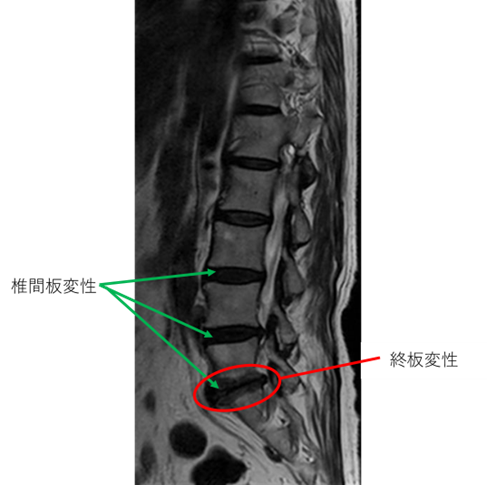

L1/2: 異常なし

L2/3: 異常なし

L3/4: 椎間板変性症、不安定症

L4/5: 椎間板変性症、不安定症

L5/S: 椎間板変性症、終板変性

以上の事が画像上認められます。

L3/4,4/5,5/s に

椎間板変性症、不安定症、終板変性 を認め、主症状の原因の可能性が高い。